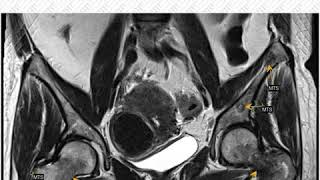

Одним из наиболее типичных проявлений остеохондроза шейного отдела является иррадиация болевых ощущений. Боль может распространяться в область плеч, рук, предплечья, кистей и пальцев. Обычно болевые ощущения сопровождаются онемением, покалыванием и слабостью в соответствующих областях.

В случае остеохондроза шейного отдела позвоночника могут возникать также мышечные симптомы. Напряжение, спазмы и слабость мышц шеи и плечевого пояса могут привести к ограничению подвижности, шейная миогелозная головная боль может отражаться в затылочно-верхнемозговой области, на затылке, в лобно-височной или височно-лобной зонах.

Нередко пациенты с остеохондрозом шейного отдела страдают дискомфортом в области живота и груди. Это может быть связано с вовлечением нервных окончаний в области шейного отдела позвоночника, что приводит к нарушению иннервации органов.

Важно отметить, что остеохондроз шейного отдела может вызывать и другие симптомы, такие как головные боли, головокружения, шум в ушах, нарушения зрения и слуха. Все эти проявления могут быть объяснены нарушением циркуляции крови и давления на сосуды и нервные структуры.